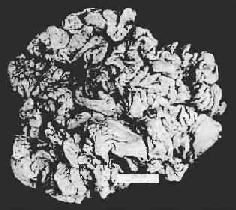

3.肥厚性胃炎(hypertrophic gastritis) 又称肥厚性胃病(hypertrophic gastropathy)、Menetrier病。发病原因不明。病变特点是,粘膜肥厚,皱襞加深变宽似脑回状(图10-5)。镜下,腺体肥大增生,腺管延长。粘膜固有层炎性细胞浸润不显著。粘膜表面粘液分泌细胞数量增加,壁细胞及主细胞有时减少。临床上,多数患者有胃酸低下及因蛋白由胃液丧失而致的低蛋白血症。

慢性肥厚性胃炎

图10-5 慢性肥厚性胃炎

胃粘膜肥厚,皱襞加深变宽似脑回状